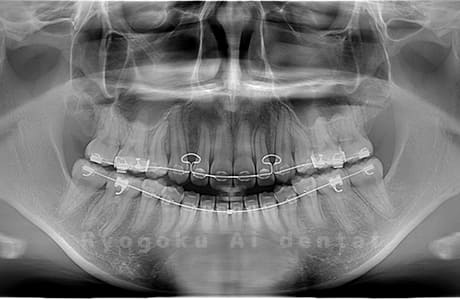

Case01

- 原因

- 水平埋伏智歯

- 治療内容

- 下顎の水平埋伏智歯を抜歯

<リスク・副作用>

手術後は痛み、腫れ、痺れなどの副作用が生じる場合があります。